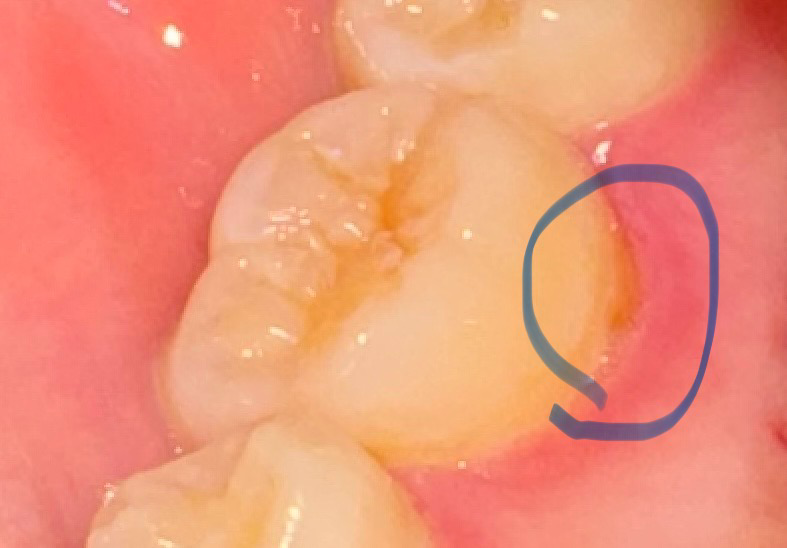

사진 속 치아 치석인가요? 혹은 충치인가요?

입을 벌려 확인해봤을때 약간 갈색비슷한 색이 보여서 썩은 줄 알고 확인해봤더니 치석같기도 하네요

• 1번 째 사진

사진에 보이는건 치석은 아니고 치경부 마모증때문에 잇몸이 내려가면서 치아의 뿌리가 노출된거 같습니다.

해당부분에 생긴 것으로 봤을 때 치석일 가능성이 높습니다만 치과에서 정확한 검진을 받아보시는 게 좋습니다.

충치의 가능성은 낮고 치태와 치석으로 보입니다 스케일링을 받은지 오래되었다면 스케일링을 한번 받아보시면 좋을 것 같습니다